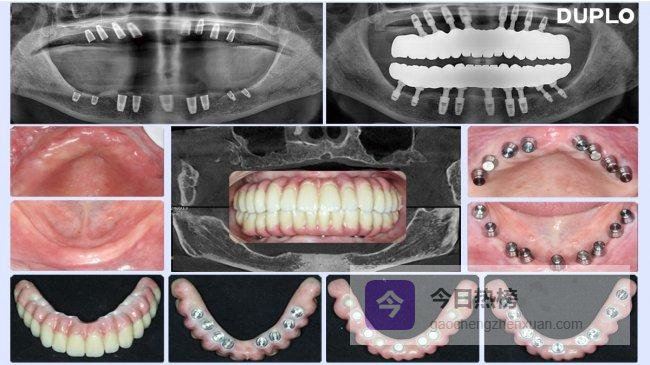

接诊后,我们首先通过CBCT进行三维影像学评估,精准测量其下颌牙槽骨可用高度仅5毫米,上颌牙槽骨脊顶宽度仅3个多毫米,伴有骨质疏松。虽然看似棘手的严重骨缺损病例,但结合往期多例类似临床经验,完全可作为多普乐解决骨量不足种植牙的适配病例,随即告知李阿姨:“您的骨条件符合多普乐超短植体适应症,无需植骨手术,采用多普乐微创种植技术即可快速完成种植。”李阿姨开心的接受了我们的治疗方案和诊疗所需费用!采用无痛局部浸润麻醉后,手术全流程仅用了52分钟。

3个多月CBCT显示植体周围骨结合均良好,顺利完成上部结构修复。“现在咀嚼效率完全恢复,硬食摄入无压力,与天然牙功能无差异。”李阿姨的临床效果,正是多普乐种植体临床优势的直观体现,也印证了无需植骨的核心价值。